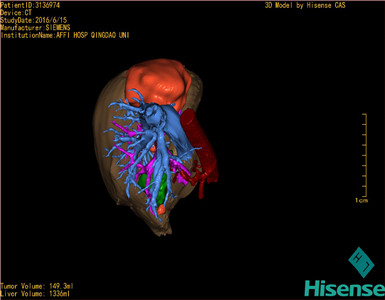

将0.625mm双源薄层CT资料的静脉期和动脉期Dicom格式文件导入海信CAS系统。

通过调节窗宽窗位调整CT序号,对肿瘤,肝实质,胆囊,下腔静脉,肿瘤,肝动脉、门静脉及肝静脉等进行三维重建;系统自动计算肿瘤体积和肝脏体积。

模拟手术操作,自动计算切除肿瘤体积。肝脏体积为1336ml,肿瘤体积为149.3ml,肿瘤体积为肝脏体积的11.2%,通过比对50-60岁正常肝脏体积为1330.41±329.13 ml,通过术前模拟手术,精准判断切除后剩余肝脏体积能耐受,避免肝衰竭发生。

术前三维重建:重建图片